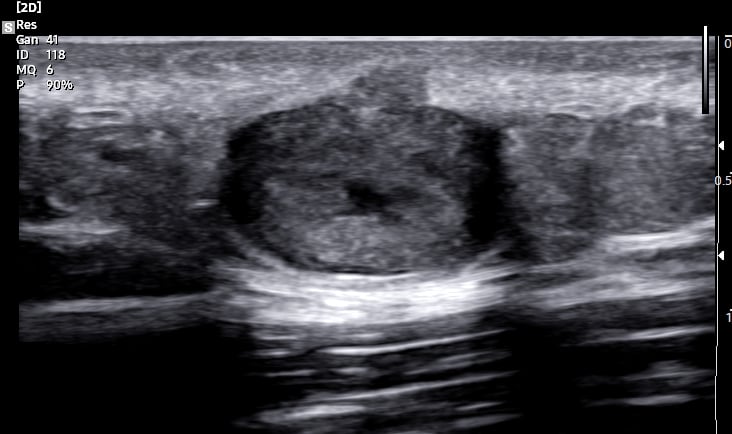

O ultrassom dermatológico é um exame não invasivo que utiliza ondas sonoras para visualizar as camadas da pele e estruturas subjacentes. Diferente dos exames convencionais, que utilizam frequências mais baixas, o ultrassom dermatológico emprega transdutores de alta frequência (acima de 15 MHz), proporcionando imagens de alta resolução da epiderme, derme e hipoderme.

A alta resolução das imagens permite diferenciar estruturas da pele, como epiderme, derme, hipoderme e possíveis lesões, facilitando a avaliação de tumores benignos e malignos, cistos, inflamações e outras alterações.